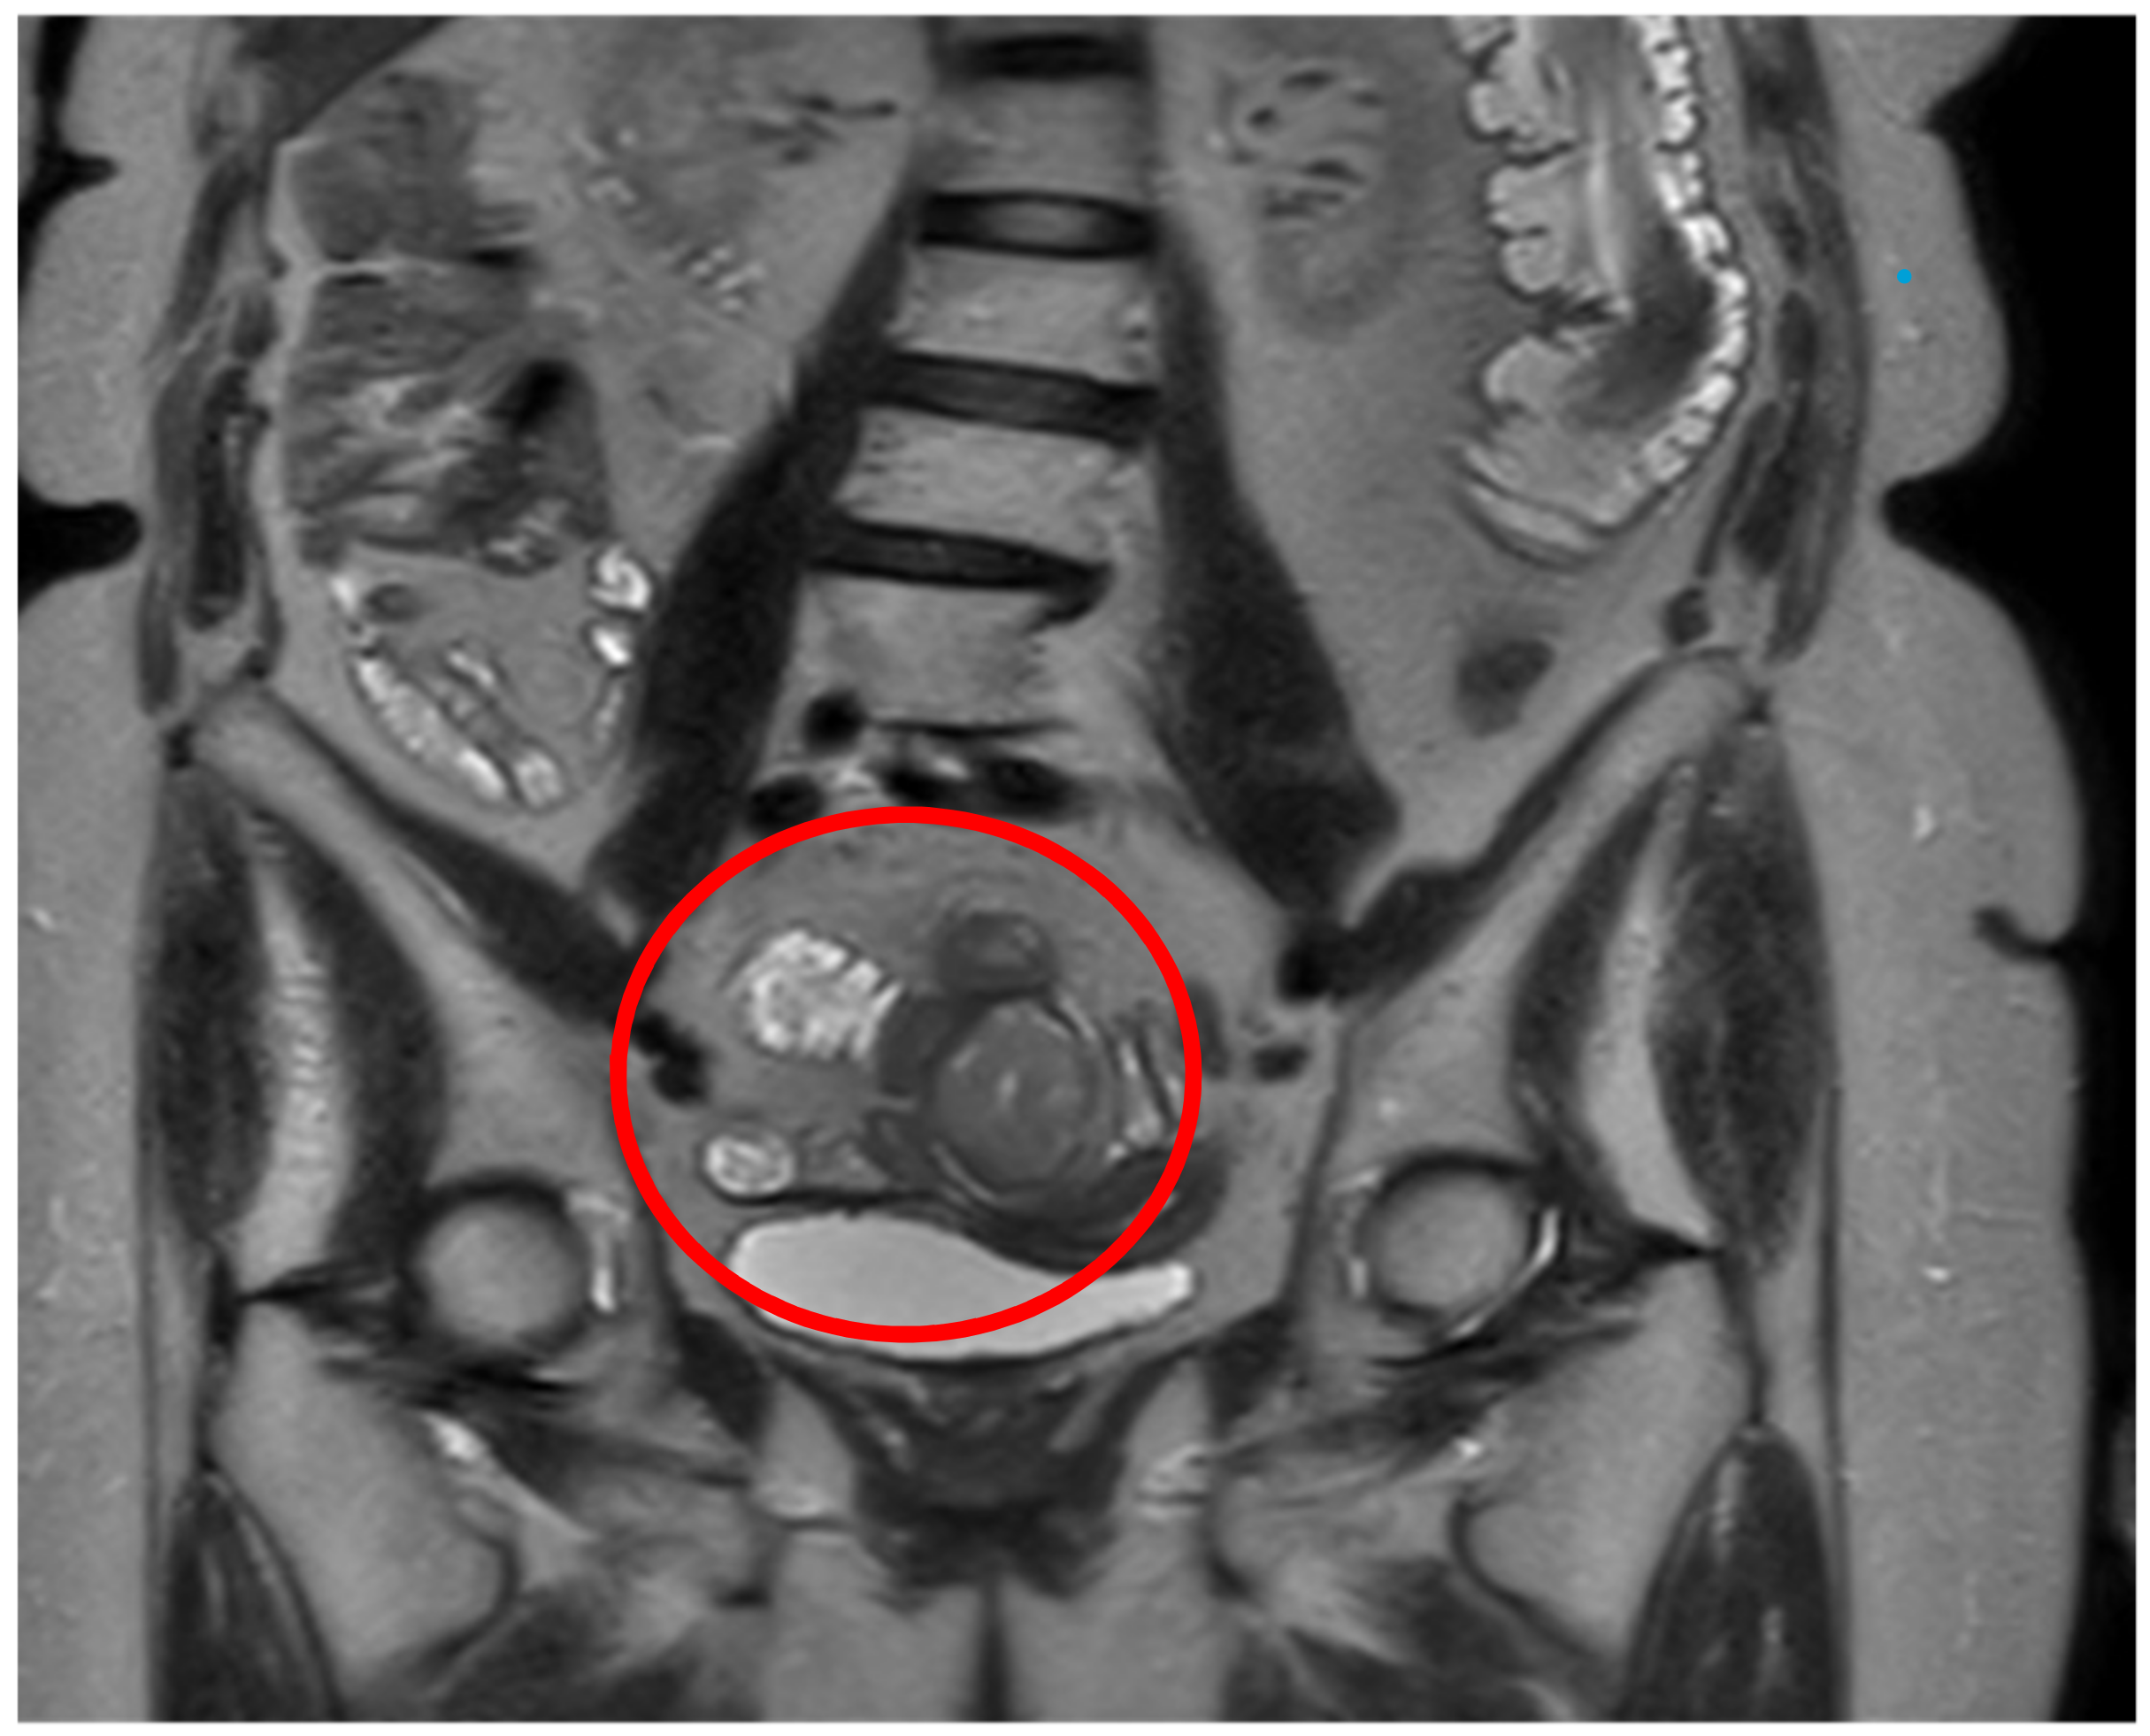

Subsequently, to further characterize the lesion, the patient underwent thoracic CT scan to complete the diagnostic staging that did not show any local lesion. Moreover, an abdominal MRI was also performed confirming the ileal mass and showing the ovarian tumor with the features of a teratoma (Figure 2). Lastly, a gynecological consultation was requested, which did not suggest any therapeutical indication for the teratoma lesion. Considering the site of the lesion, any kind of endoscopy could be performed to obtain preoperative biopsies.

Figure 2.

The circle shows the mass on MRI.